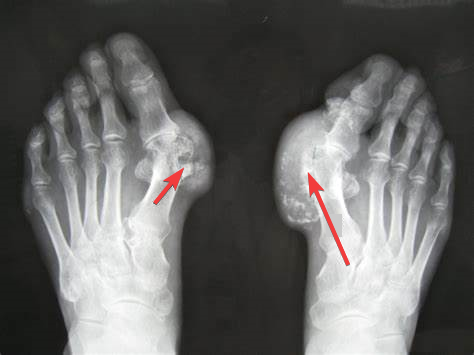

痛风在间歇期可通过饮食控制和药物治疗有效控制病情发展,但大部分痛风患者依从性差,长期高尿酸血症状态及急性痛风反复发作是引起尿酸沉积形成痛风石的主要原因。痛风性关节炎大多受累于第一跖趾关节(即大脚趾关节处),其他受累关节分别为足背、踝、膝、指、腕等关节,臀部痛风石较为少见。对于巨大痛风石严重影响生活质量的患者,可行痛风石切除术治疗,但其具有过程复杂、易感染、多伴并发症、易复发等特点。

患者男,62岁[2]。既往30+年“痛风”病史,10+年前因双足多发痛风石曾于“外院”行手术治疗(具体不详),现四肢远端见多发痛风石,手指、足趾肿胀严重畸形,活动明显受限,未诉肢体关节疼痛。其母亲及兄弟有痛风病史。此次因“发现双侧臀部肿物10+年,加重伴左侧疼痛6+个月”。10+年前患者无明显诱因发现双侧臀部肿物,左侧大小约7cm×6cm, 右侧约4cm×3cm, 质韧,可推动,与周围组织无粘连,患者未予重视,未经系统诊治。6+个月前患者无明显诱因感臀部肿物较前增大,伴左侧疼痛、活动障碍,左侧大小约10cm×10cm, 右侧约6cm×5cm, 质韧,可推动,与周围组织无粘连。严重影响日常生活,遂就诊于我院风湿免疫科门诊,因左臀部单个痛风石体积大、质地硬,并已造成关节功能障碍,无法独立步行,已不能通过保守治疗达到满意的治疗效果,与患者本人与家属进行了充分的沟通,拟收治入院行手术治疗。

辅助检查:实验室检查:中性粒细胞百分比79.30%,淋巴细胞百分比12.90%。尿素 17.39mmol/L,肌酐130.0μmol/L,尿酸 602μmol/L,估算肾小球滤过率51mL/(min·1.73m2)。血沉、CRP、肝功能未见明显异常。尿常规pH值5.00。盆腔螺旋CT回示(见图1):右肾小结石;多发关节周围、臀部软组织高密度影及骨质改变。左侧浅表包块彩超回示(见图2):左侧臀部皮下组织混合回声团,请结合临床。诊断:(1)皮下组织肉芽肿(左侧臀部痛风性肉芽肿),(2)右侧臀部肿物,(3)全身多发痛风石形成,(4)原发性高血压3级 很高危组并心脏损害,(5)冠状动脉粥样硬化性心脏病,(6)冠状动脉支架植入后状态,(7)2型糖尿病,(8)慢性肾衰竭。